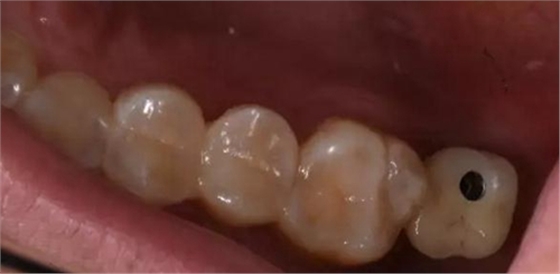

術后口內(nèi)照片

修復體戴入口內(nèi)后照片,與鄰牙鄰接良好。